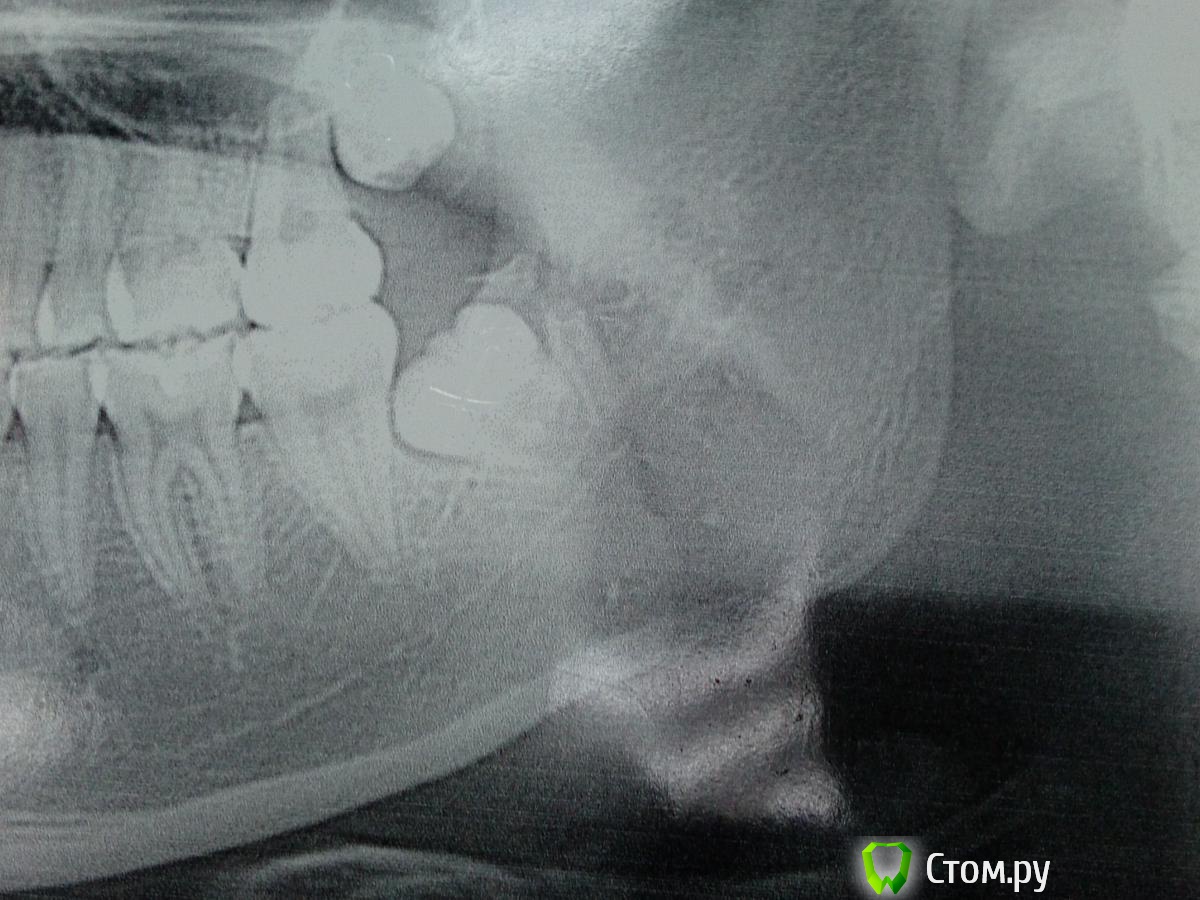

Andex Опубликовано 27 января, 2014 Поделиться Опубликовано 27 января, 2014 (изменено) Рутина из работы хирурга - удаление 28 зуба, но тут под руку попался еще и 29! редко их встречаю, решил поделиться.Панорама до удаления сидели там треугольником 27,28,29. Теперь остался 27. А на очереди 19 ! Изменено 27 января, 2014 пользователем Andex 1 Ссылка на комментарий